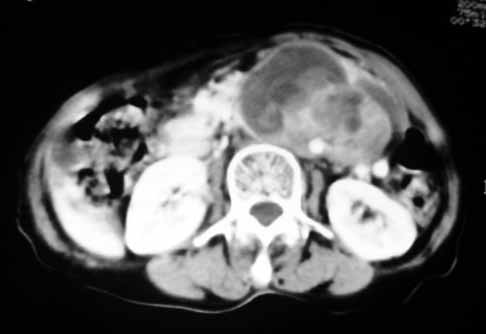

以下是引用天南地北在2007-4-30 17:42:00的发言:[br]增强扫描显示腹主动脉给包绕、推移。肿块不规则强化,[br]修正我在平扫的诊断[br]支持考虑:间叶源性肿瘤可能性大

以下是引用余辉在2007-4-30 18:01:00的发言:[br]病灶前方的条状增强影是什么?若是胰腺,位置似乎有点低,若是十二指肠,似乎又不诫该是那样强化,姑且将其看作胰腺吧,那么考虑来源于胰腺粘液囊腺瘤可能性大,其次考虑来源于肠系膜或者后腹膜的肿瘤如平滑肌肉瘤,异位嗜铬细胞瘤及淋巴瘤等。

以下是引用zyx168在2007-4-30 23:24:00的发言:[br]考虑:间叶源性肿瘤可能性大